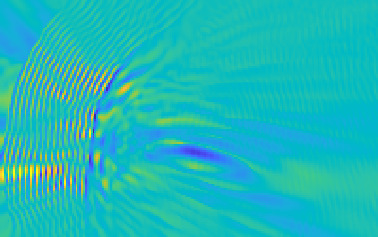

Model-based treatment planning for transcranial ultrasound therapy typically involves mapping the acoustic properties of the skull from an x-ray computed tomography (CT) image of the head. Here, three methods for generating pseudo-CT images from magnetic resonance (MR) images were compared as an alternative to CT. A convolutional neural network (U-Net) was trained on paired MR-CT images to generate pseudo-CT images from either T1-weighted or zero-echo time (ZTE) MR images (denoted tCT and zCT, respectively). A direct mapping from ZTE to pseudo-CT was also implemented (denoted cCT). When comparing the pseudo-CT and ground truth CT images for the test set, the mean absolute error was 133, 83, and 145 Hounsfield units (HU) across the whole head, and 398, 222, and 336 HU within the skull for the tCT, zCT, and cCT images, respectively. Ultrasound simulations were also performed using the generated pseudo-CT images and compared to simulations based on CT. An annular array transducer was used targeting the visual or motor cortex. The mean differences in the simulated focal pressure, focal position, and focal volume were 9.9%, 1.5 mm, and 15.1% for simulations based on the tCT images, 5.7%, 0.6 mm, and 5.7% for the zCT, and 6.7%, 0.9 mm, and 12.1% for the cCT. The improved results for images mapped from ZTE highlight the advantage of using imaging sequences which improve contrast of the skull bone. Overall, these results demonstrate that acoustic simulations based on MR images can give comparable accuracy to those based on CT.